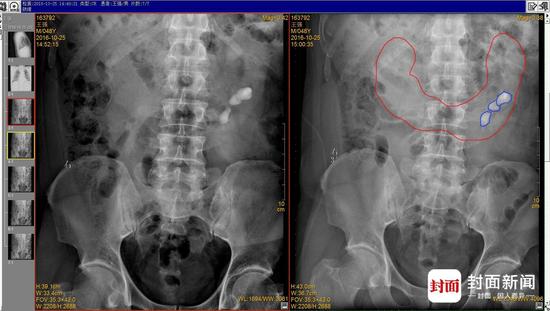

男子長(zhǎng)U形馬蹄腎:術(shù)前X光畫(huà)紅色為馬蹄腎基本輪廓,藍(lán)色為結(jié)石輪廓

10月28日,最終醫(yī)生將王先生體內(nèi)4顆直徑超過(guò)1厘米,最大近2厘米的結(jié)石,順利粉碎并取出。“他的手術(shù)進(jìn)行了大約4個(gè)小時(shí),比普通經(jīng)皮腎鏡手術(shù)多了一倍時(shí)間,手術(shù)難度還是比較大的。”許卓感嘆說(shuō)。